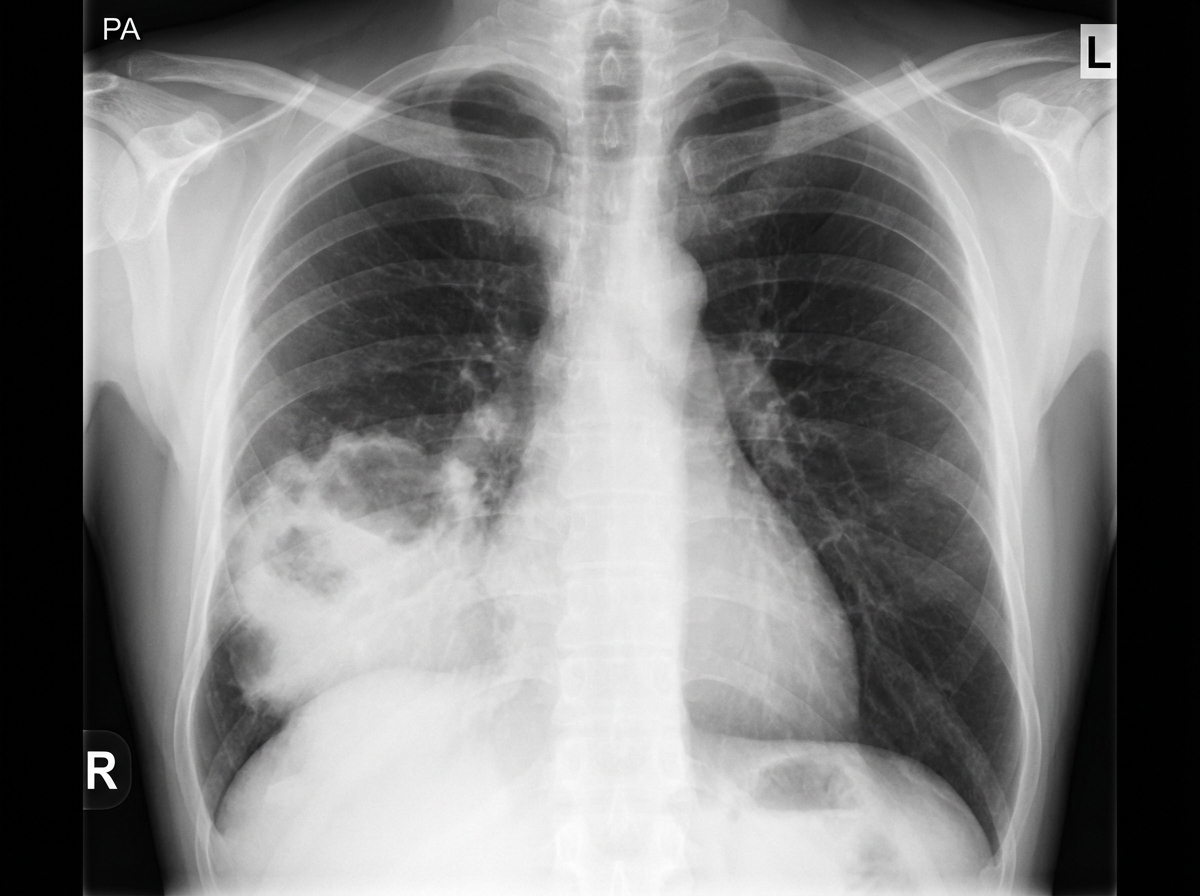

A 55-year-old woman comes to the physician because of a 4-day history of chest pain and cough with rust-colored sputum. The chest pain is sharp, stabbing, and exacerbated by coughing. Ten days ago, she had a sore throat and a runny nose. She was diagnosed with multiple sclerosis at the age of 40 years and uses a wheelchair for mobility. She has smoked a pack of cigarettes daily for the past 40 years. She does not drink alcohol. Current medications include ocrelizumab and dantrolene. Her temperature is 37.9°C (100.2°F), blood pressure is 110/60 mm Hg, and pulse is 105/min. A few scattered inspiratory crackles are heard in the right lower lung. Cardiac examination shows no abnormalities. Neurologic examination shows stiffness and decreased sensation of the lower extremities; there is diffuse hyperreflexia. An x-ray of the chest is shown. Which of the following is the most likely cause of her current symptoms?